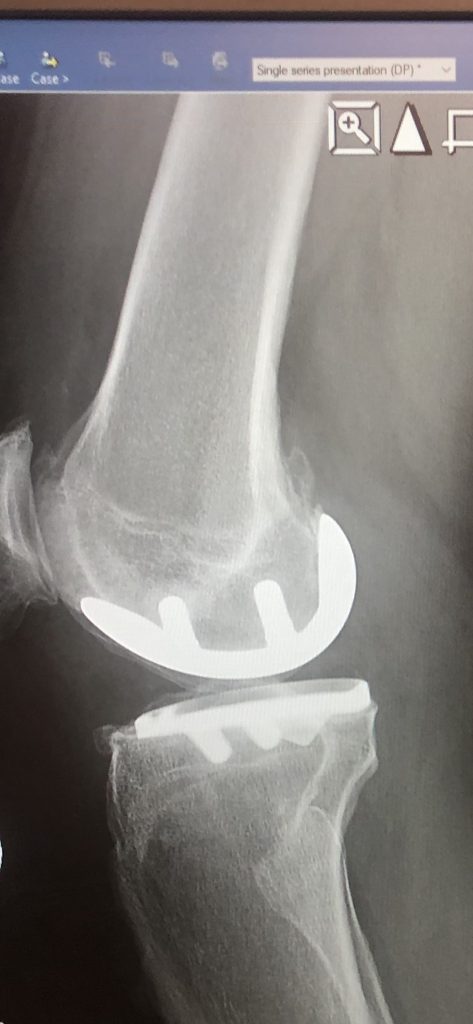

Instead of replacing my whole knee, Dr. Nawabi was able to save 2/3's of my knee. 6 months after surgery I have very little pain and enjoy an active lifestyle. I have provided pictures of my bone on bone knee prior to surgery and the partial knee replacement 6 months after surgery. I even hiked in the Rocky Mountain National Park just 10 weeks after surgery.